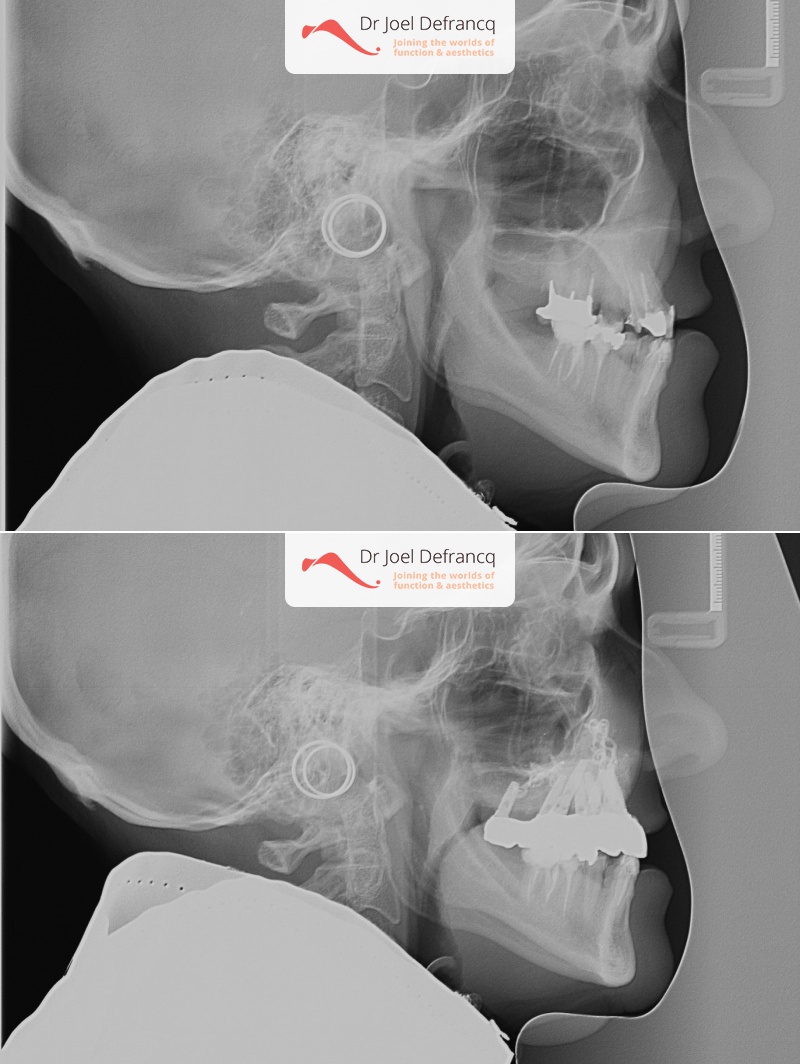

Vitali: upper jaw too far back - jaw surgery & implants.

- Klasse III

Kaakchirurgie

- Verlenging bovenkaak (Le Fort I)